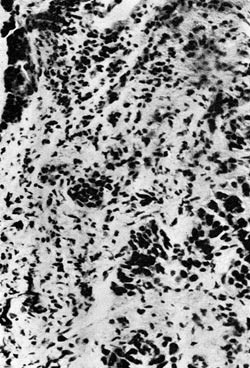

Ved retrograd ureterografi lot det seg ikke gjøre å presse kontrast lenger opp enn nedre kant av venstre iliosakralledd. R: «Hindret passasje i venstre ureter» (fig. 2).